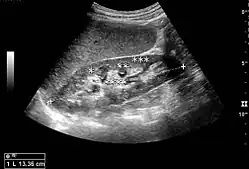

The kidney is divided into parenchyma and renal sinus. The renal sinus is hyperechoic and is composed of calyces, the renal pelvis, fat and the major intrarenal vessels. In the normal kidney, the urinary collecting system in the renal sinus is not visible, but it creates a heteroechoic appearance with the interposed fat and vessels. The parenchyma is more hypoechoic and homogenous and is divided into the outermost cortex and the innermost and slightly less echogenic medullary pyramids. Between the pyramids are the cortical infoldings, called columns of Bertin (Figure 1). In the pediatric patient, it is easier to differentiate the hypoechoic medullar pyramids from the more echogenic peripheral zone of the cortex in the parenchyma rim, as well as the columns of Bertin (Figure 2).[1]

Figure 2. Normal pediatric kidney. * Column of Bertin; ** pyramid; *** cortex; **** sinus.[1] -